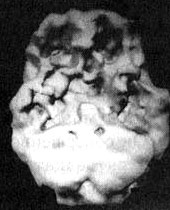

Мозг Роба. Алкогольная, кокаиновая и метамфетаминовая зависимость

Трехмерное изображение поверхности, вид сверху. Обратите внимание на выраженное улучшение после годового воздержания от алкоголя и наркотиков.